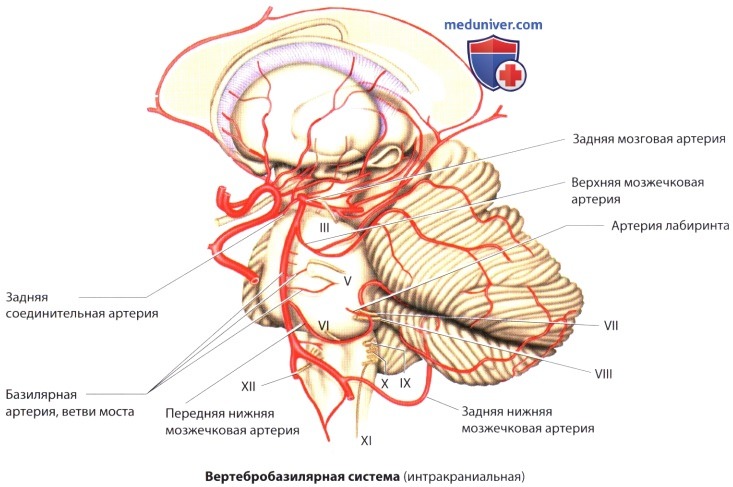

Анатомия: Задняя соединительная артерия мозга